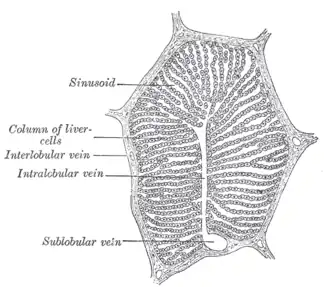

A single lobule of the liver of a pig. X 60. (Central vein not labeled, though region is visible. Central vein would be a single vein at the center of the lobule.) | |

In microanatomy, the central vein of liver (or central venule)[1] is a vein at the center of each hepatic lobule.[2] It receives the blood mixed in the liver sinusoids to drain it into hepatic veins.[3]